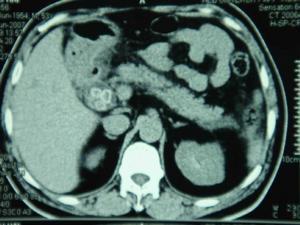

膽總管結石CT顯示疾病病因

4.CT斷層掃描CT對膽總管結石的診斷優於B超,準確率可達80%左右。但難以顯示膽管系統病理改變和結石數量、大小、分布等狀況。